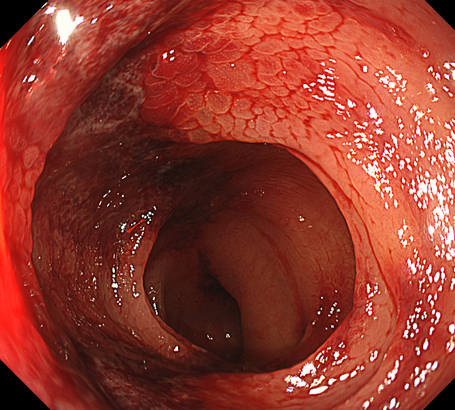

虚血性大腸炎とは何らかの原因で突然、または一過性の血流障害が生じて、大腸の粘膜に十分な血液が行き届かなくなる(虚血状態になる)腸炎を指します。

左側大腸(下行結腸~S状結腸)に生じることが多いと言われています。

突然の強い腹痛に続いて下痢が起こり、徐々に血便がみられるようになるのが典型的と言われています。また、左側大腸に生じることが多いので左側優位の腹痛が起こることも特徴的です。

• 内視鏡検査